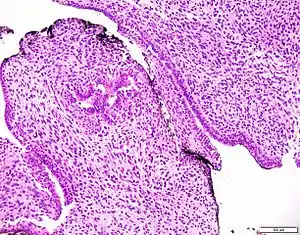

Prostatic stromal tumour of uncertain malignant potential. H&E stain.

Prostatic stromal tumour of uncertain malignant potential (PSTUMP) is a rare tumour of the prostate gland stroma that may behave benign or like cancer.